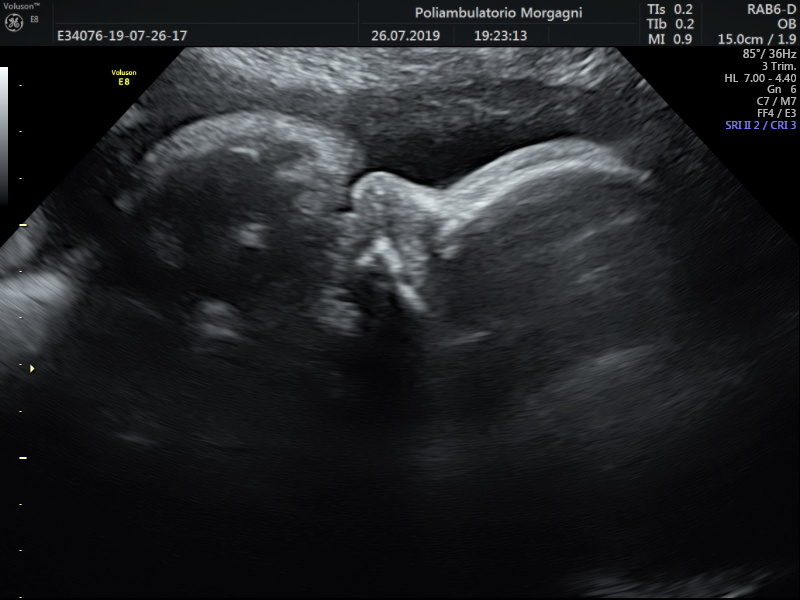

Nel caso che il tesoro, nelle ecografie precedenti, sia risultato un po’ sovrappeso o un po’ sottopeso, sarebbe meglio eseguire una ulteriore valutazione della crescita fetale e del benessere fetale fra la fine dell’ottavo o l’inizio del nono mese.